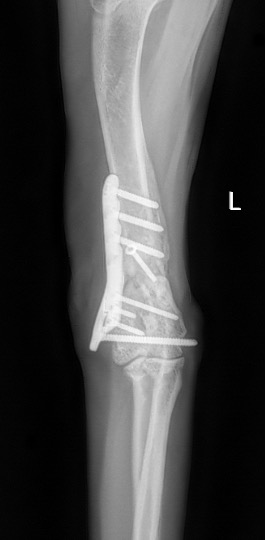

Exemple 1 :

Figure 1 : Pré-op

Figure 2 : Post-Op Immédiat